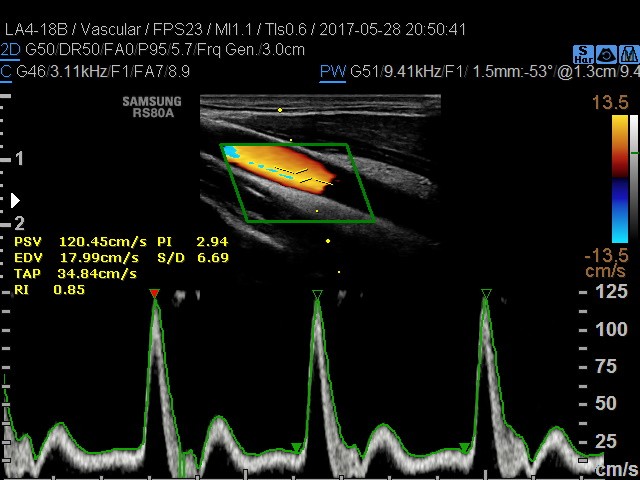

• USG tętnic szyjnych i kręgowych

• USG doppler tętnic kończyn górnych i dolnych